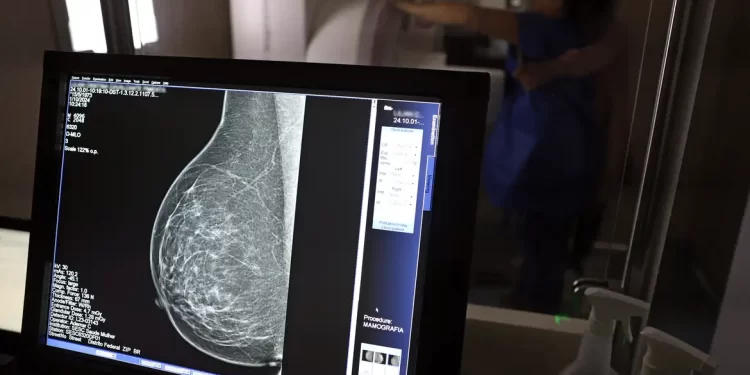

Para a entidade, os números reforçam a importância de ampliar o rastreamento do câncer de mama por meio da realização de mamografia em mulheres abaixo dos 50 anos e acima dos 70 anos, faixas etárias que não estão incluídas na recomendação padrão de exames preventivos no âmbito do Sistema Único de Saúde (SUS).

O levantamento mostra que, entre janeiro de 2018 e dezembro de 2023, o Brasil registrou mais de 319 mil diagnósticos de câncer de mama, sendo 157,4 mil em mulheres de 50 a 69 anos, faixa etária atualmente recomendada para o rastreamento.

Entre mulheres com idade entre 40 e 49 anos, foram registrados 71.204 casos de câncer de mama, enquanto 19.576 mulheres com idade entre 35 e 39 anos também receberam o diagnóstico da doença. Juntas, ambas as ocorrências representam 33% do total de casos diagnosticados no período.

Já entre mulheres acima de 70 anos, foram identificados 53.240 casos de câncer de mama.